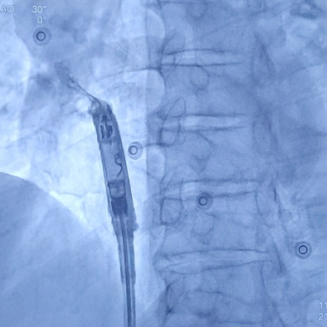

心房无导线起搏器最终植入位置

手术首先利用电生理四极导管标测Bachmann束区域,留影做参考;再次利用保护套筒造影精准确认植入位置,后退保护套筒,将心房无导线旋入1.5圈,参数良好且稳定。